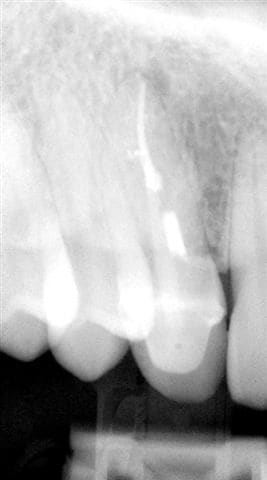

-La seule "nouvelle" technologie qui semble enfin acceptée par le plus grand nombre d'entre nous est l'implantologie, à tel point que des abus sont faits, à savoir extractions intempestives de certaines dents tout à fait conservables grâce à la paro ou l'endo cf radios ci-joint, la dernière ayant été faite un an après le traitement ("madame, votre canine est infectée de façon très importante, on ne peut pas la sauvée, nous allons l'extraire et poser un implant"...)

016 iz9c3d - Eugenol

021 qxjakd - Eugenol

004 s729bo - Eugenol